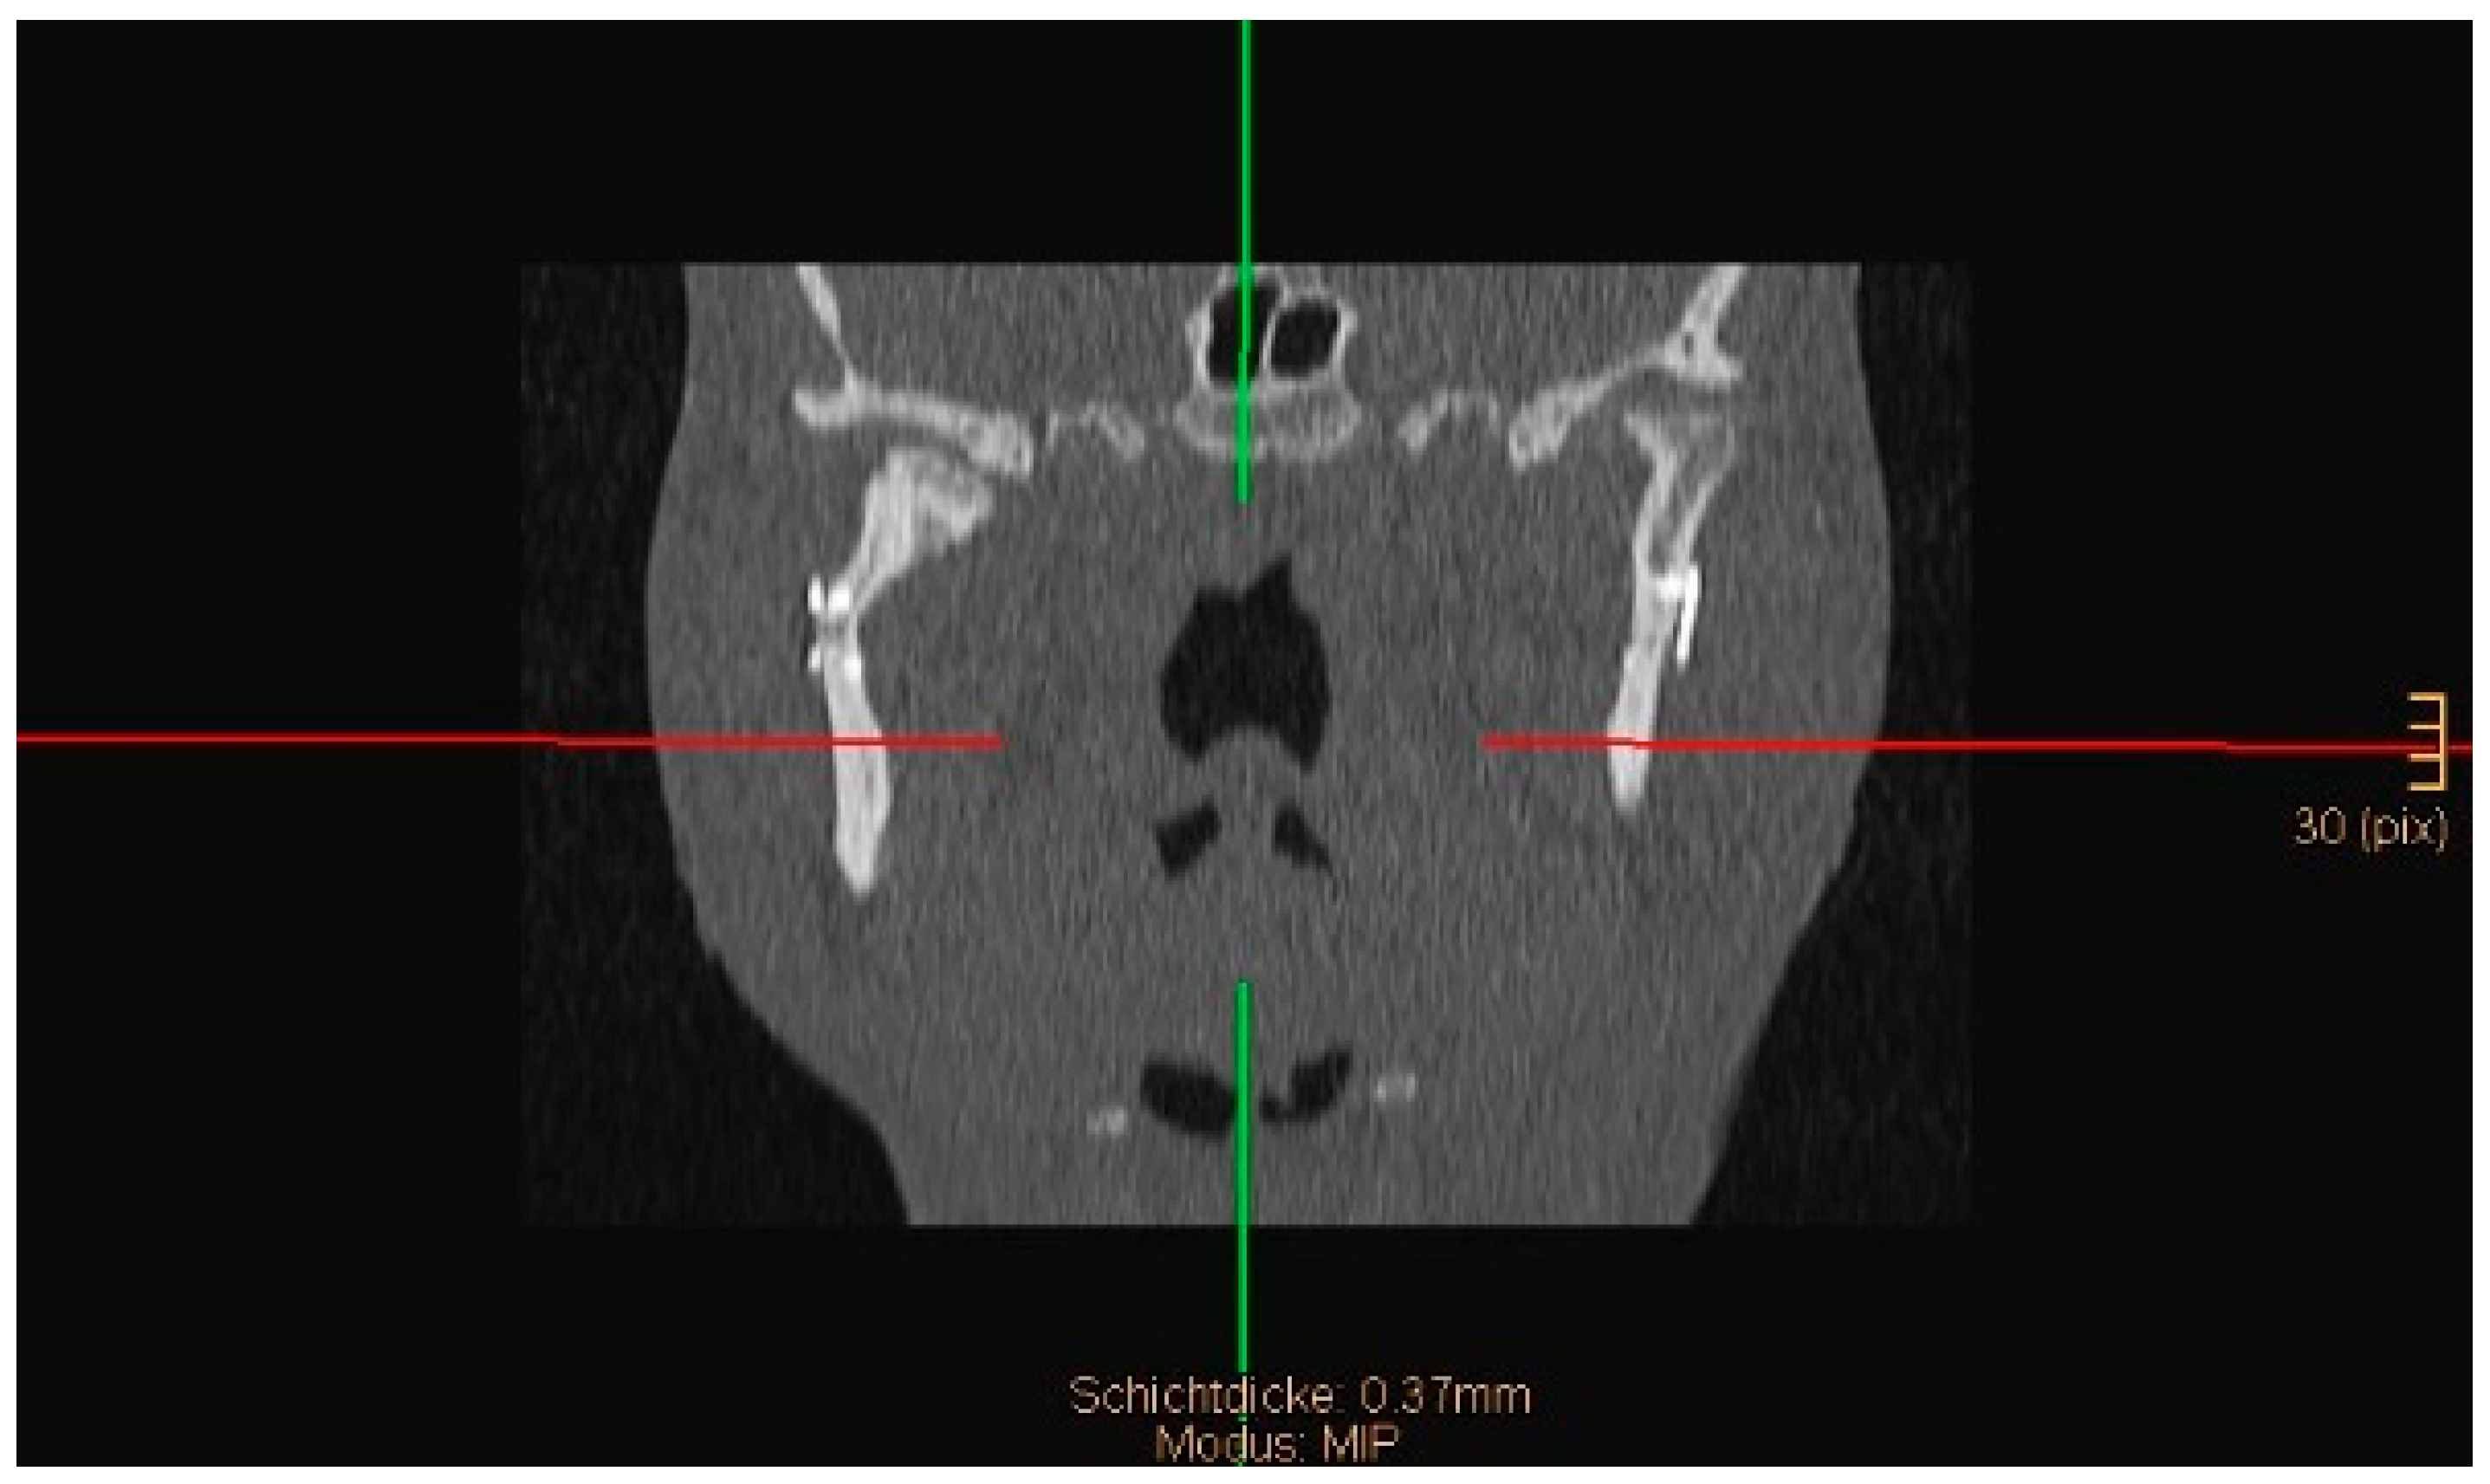

The angle between the condylar neck and the ramus after ORIF on the coronal view of a computed tomogram (CT) was measured. A postoperative angulation of less than 10° was considered good, 10–45° was considered acceptable, and >45° was considered insufficient.

Two operations had to be redone because of inadequate reposition in the symphysis/parasymphysis with broad (>2 mm) lingual splay. In both cases, straight miniplates were removed. Osteosynthesis was achieved with lag screws. Figure 3 depicts plate osteosynthesis of a symphyseal fracture with a broad lingual gap (Figure 3). Figure 4 shows the same patient after redo operation and osteosynthesis of the same fracture with a lag-screw and a marked reduction in the lingual splaying (Figure 4). Figure 5 demonstrates the condylar reduction in the frontal plane in the same patient. Figure 6 and Figure 7 show the patient’s occlusion (Figure 5, Figure 6 and Figure 7). The third redo operation was due to nonunion and infection of an angular fracture with fracture of the two condylar plates. In this case, after removal of the infected miniplate, the angle fracture was stabilized with a reconstruction plate and a miniplate from an extraoral approach; the two broken miniplates at the condylar process were left in situ.

Figure 8 and Figure 9 below show another patient with a non-satisfactory reduction in the condylar neck fracture on the left-hand side due to a lingual gap present at a body fracture (Figure 8 and Figure 9).

Figure 5. Coronal CT scan showing both condyles after ORIF. A widening of the mandible, caused by a small lingual gap that persisted even after lag screw osteosynthesis at the symphysis, resulted in an angulation of the condylar neck on the right-hand side (same patient as in Figure 3 and Figure 4). The image shown was taken on the third postoperative day after drainage removal and the situation did not worsen over time (last follow-up 1 year postop).

Figure 8. Coronal CT scan showing a condylar neck angulation on the left side after ORIF. An anatomical reduction could not be achieved.

Figure 9. Axial CT scan showing the same patient as in Figure 8. A lingual gap is present after ORIF of the mandibular body fracture, contributing to the inability to reduce the condylar fracture correctly.